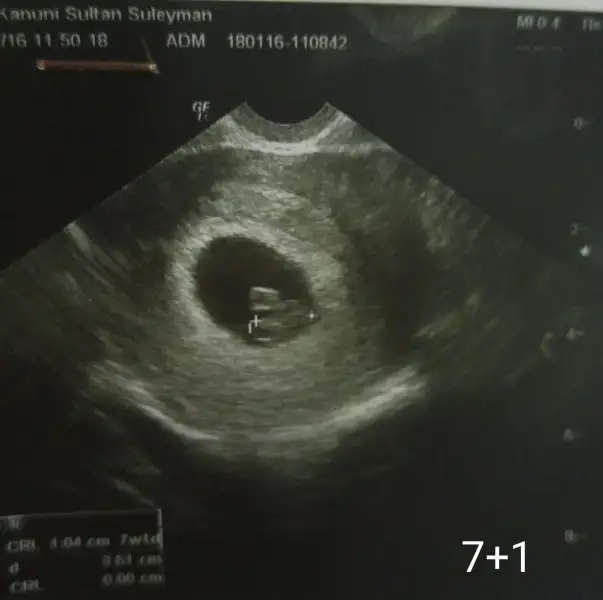

Ne kadar çok şey varmış ya ikili teste göre cinsiyeti bile duydum ama plasentaya göre hiç duymadım. Yükledim canım merak ettim valla doğru çıkacak mı gerçi benimki belli ama test etmiş oluruz:) o etraftaki beyazlığı bende plasenta sanıyordum.

Canım karından mı bu gürüntü, vajinal mi? Ben de işini ustasına devrediyorum, arch2401 arch2401 yorumlar mısın lütfen:)

daha net bir görüntü var mı ? kesenin içindeki hiçbirşeyi seçemiyorum.

Hem vajinal hem karından da bakmıştı canım ama bu hangisi bilmiyorum telimde varken biliyordum da sildim sonra şimdi yineden çektim:KK57: çok farkeder mi ki?

karından veya vajinal olması farkediyor çünkü yönler 180 derece farklı vajinalde sağ olan karından sol oluyor vb..

ters köşe yaptın beni sağdan soldan öte aşağıya yakın ama sağ aşağı olduğu için tahminim plesanta sağ yerleşkeli ve bu da vajinalde ramziye göre erkek olma olasılığı görünüyor.